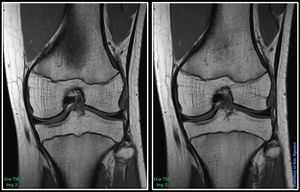

Take a closer look at the sharpness between img 1 and img 2. The slice position is almost the same, sorry for that. However, it shows clearly what image is the sharpest. TR and scantime almost the same. BW, TE, FOV, inter echo spacing, ETL, ipat, interpolation, slice thickness etc. the same. One important parameter determining sharpness of the images would be?#s_mri #mri#siemens